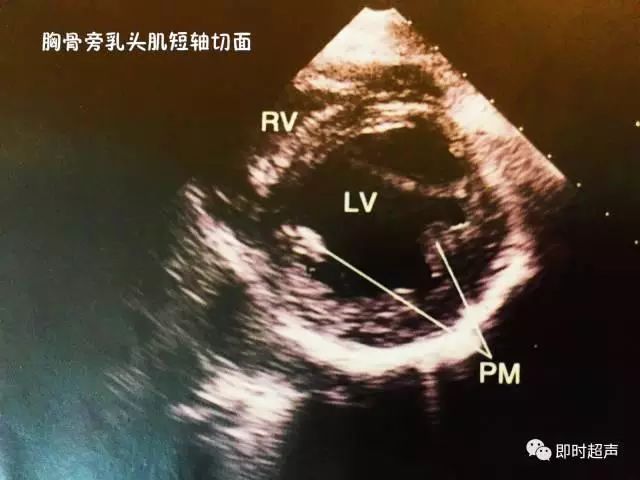

五、胸骨旁乳头肌短轴切面

主要观察:左心室壁及乳头的病变和测量心腔面积。